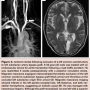

Postoperative ischemic strokes are most commonly focal and occur as a result of small emboli from extracranial sources, including carotid and arch atheroma or cardiac arrhythmias. Large watershed infarcts may also occur following large emboli or exclusion of the origins of the aortic arch branches. The functional patency of the Circle of Willis is an important collateral pathway (Figure 1).